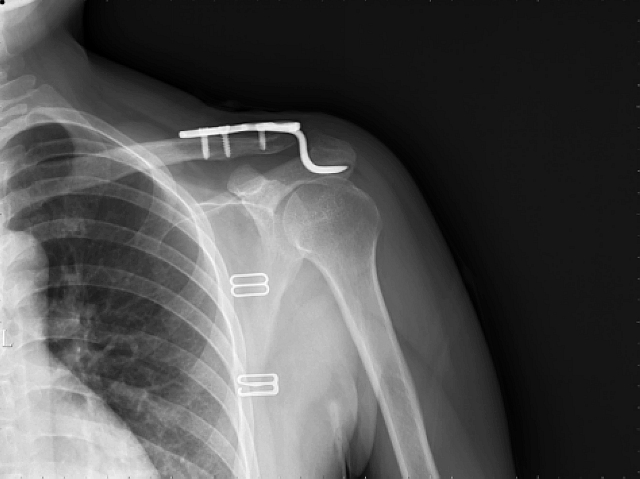

可调节带袢钢板有限切开内固定术后

传统锁骨钩钢板切开复位内固定术(需二次行内固定物取除)。